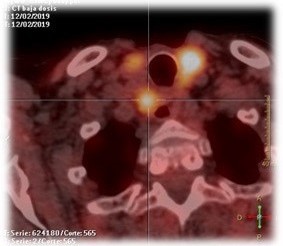

Cervical ultrasound, 18F-choline PET-CT, and 99mTc-sestamibi scintigraphy identified a hyperfunctioning parathyroid lesion (6×4 cm) in the left thyroid lobe, extending into the retroesophageal space, mediastinum, and thoracic vertebra T3. Suspecting parathyroid carcinoma, en bloc resection was performed, including four anterior and posterior mediastinal lymph nodes. Sternotomy was required for complete excision.

Figure 4: PET-CT with 18F-Choline: hyperfunctioning parathyroidlesión.